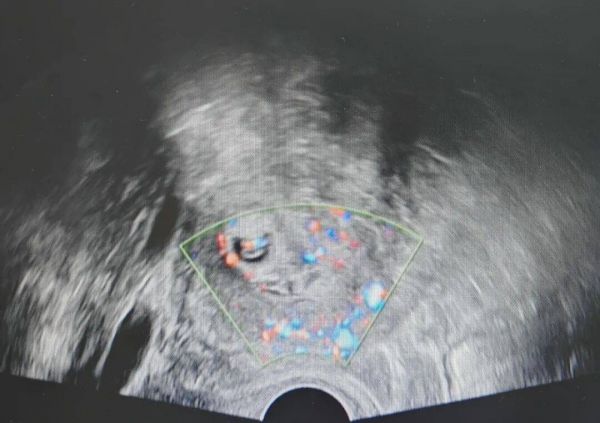

该患者异常阴道出血长达2个月,辗转就医未查明病因,来院后经检查确诊妊娠,且孕囊位置极其凶险。结合检查结果,孕囊着床于宫腔偏右侧宫角处,加之患者有两次剖宫产史,子宫瘢痕肌层薄弱,而宫角部位血运丰富、肌层菲薄,随时可能破裂引发大出血,病情万分危急。

宫角妊娠堪称子宫角落的“定时炸弹”,作为异位妊娠中极凶险的类型,该部位血管密布,一旦破裂,短时间内就会引发致命性大出血、失血性休克,死亡率远超普通宫外孕。叠加患者剖宫产病史,子宫结构异常、粘连风险高,进一步加大了诊疗与手术难度。